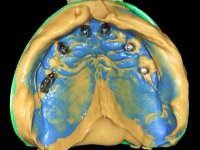

Realizada uma TAC, foi planificada a colocação de 6 implantes no maxilar superior. Foi decidida a colocação de dois implantes na zona dos incisivos centrais, dois implantes na zona dos caninos e dois na zona dos segundos pré-molares. A ausência de estrutura óssea na zona distal do primeiro quadrante implicava a realização de uma regeneração óssea no seio maxilar direito. A cirurgia foi realizada e após a colocação dos implantes foi feita a impressão para confeção de uma prótese provisória metalo-acrílica aparafusada para colocação em carga imediata no dia seguinte. O implante colocado na zona do seio maxilar direito não foi colocado em carga. Passados 6 meses foi realizada a impressão aos 6 implantes com técnica de moldeira aberta e foram confecionados os modelos de trabalho. Numa consulta seguinte foram montados os modelos de trabalho em articulador semi-ajustável utilizando o arco facial e a relação inter-maxilar obtida com a prótese provisória. Foi feita uma muralha de silicone sobre a ponte provisória com o objetivo de orientar o trabalho laboratorial. Realizada a infra estrutura metálica aparafusada esta foi provada em boca e finalmente após colocação de cerâmica o trabalho foi colocado definitivamente. Como passaram vários meses após a realização da primeira TAC foi feita uma segunda para planificar a colocação de implantes no 4º quadrante. Colocaram-se 3 implantes na mesma sessão em que foi feita a extração dos pilares da ponte. Estes implantes foram posteriormente reabilitados com uma ponte metalo-cerâmica aparafusada de três elementos.